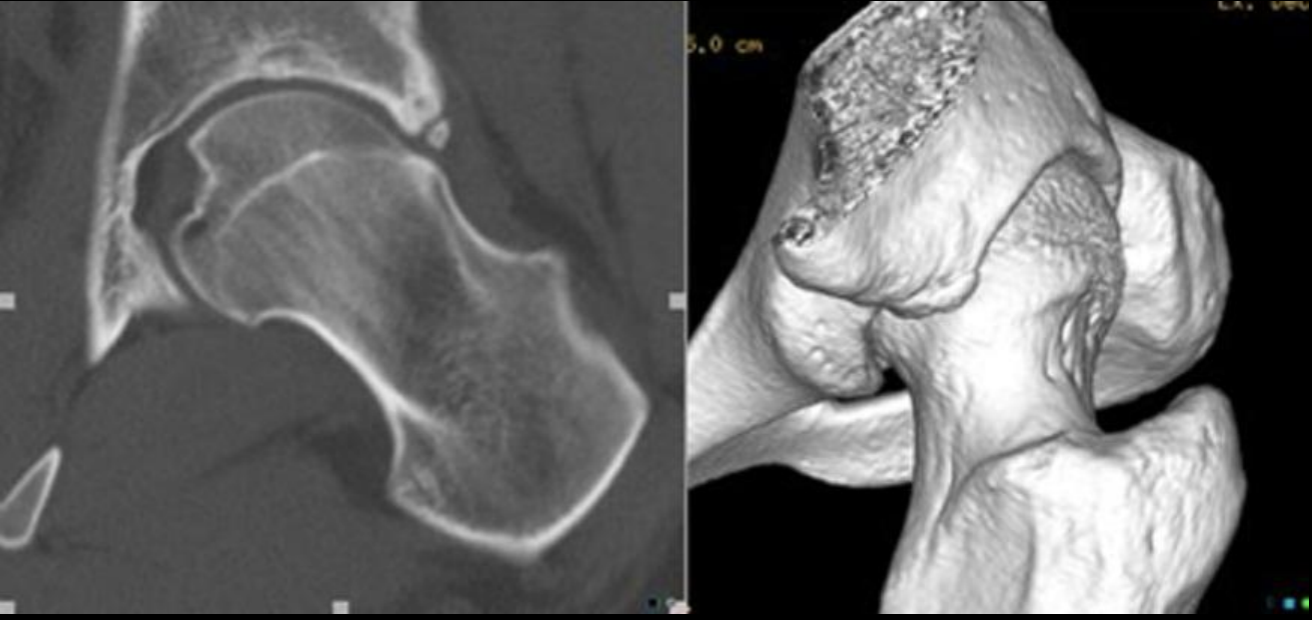

TC en pinzamiento femoroacetabular

A

Permite evaluación anatomica

Reconstrucción 3D

Reconstrucción 3D CAM